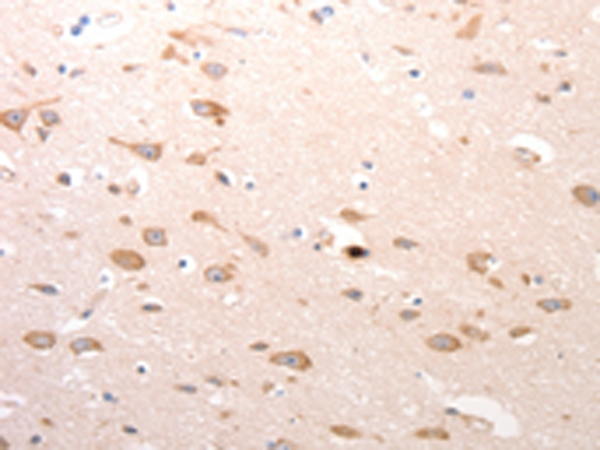

分类: 科研抗体货号: P10729别名: CASP-12, CASP12P1应用: WB,IHC反应种属: Human, Mouse